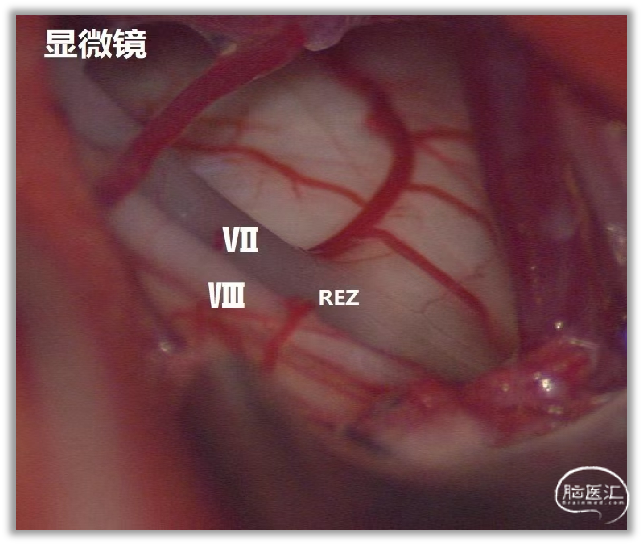

▼15.小脑绒球下入路

小脑绒球下入路(infrafloccular approach)最早由日本专家Matsushima提出。因为绒球和从Luschka孔突出的脉络丛从外侧遮挡面神经REZ区(下图),而且,在绒球和前庭蜗神经之间经常有黏连,还可能存在大量坚韧的蛛网膜小梁,因此从小脑外侧间隙很难暴露REZ区,还可能造成听力损伤。

绒球下入路(上图)就是抬起小脑的下外侧缘,打开舌咽神经和迷走神经后方的蛛网膜,便可暴露由Luschka孔突出的位于舌咽神经和迷走神经后面的脉络丛,将脉络丛从舌咽神经后缘轻轻分开,以暴露舌咽神经与脑干连接处。脑板进一步向上将脉络丛从舌咽神经后缘上抬起,暴露范围向舌咽神经上方扩展数毫米,此处即为面神经与脑干的连接处(REZ区),恰位于前庭蜗神经的前下方。

▼内镜下不需过多牵拉和剥离神经组织即能清晰地显露REZ区